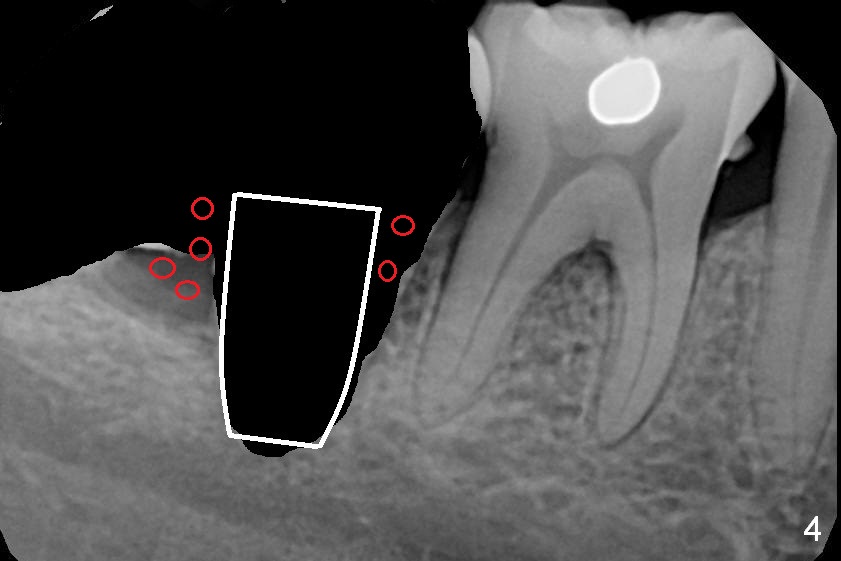

A 39-year-old woman has pain and mobility associated with the tooth #31 (Fig.1 (taken 5 months earlier), 2). It is easy to extract the mesioangularly impacted third molar (#32) after extraction of #31. After debridement and Clindamycin socket disinfection, collagen plug is placed in #32 socket, while allograft in the bottom half of the #31 one. The most coronal portion of the sockets are packed with mixture of collagen and Osteogen plugs and fixed in place with 4-0 Chromic gut (Fig.3). Two or 3 months postop, use #15 to start bone expansion at #31, followed by osteotomes or bone expanders and Tatum tapered taps. Take preop X-ray for depth measurement. The socket is close to the Inferior Alveolar Canal. In one word, no drill will be used for osteotomy. Place bone graft (Fig.4 red circles) prior to implant placement (white outline). Take CT post implant placement to confirm that the Inferior Alveolar Nerve is lingual to the implant.